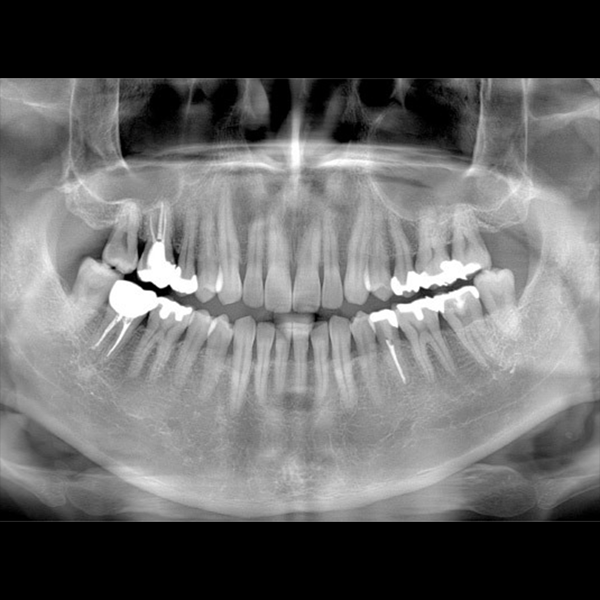

従来の2次元パノラマ画像

3次元CT画像

3次元CT画像を自由に動かして、あらゆる方向から診断する事ができます